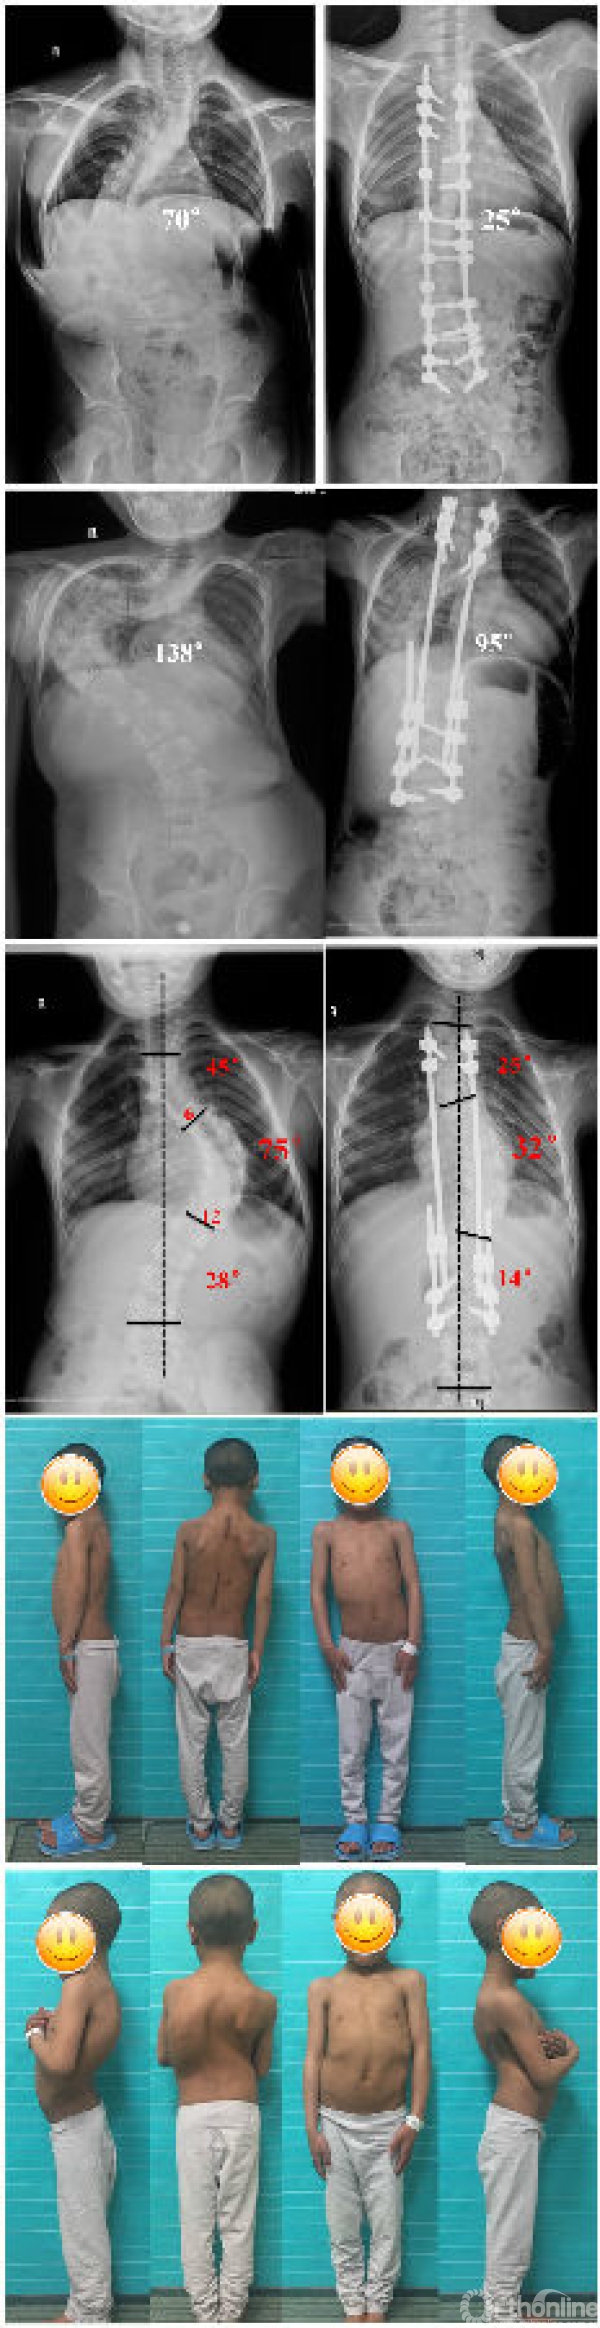

病例